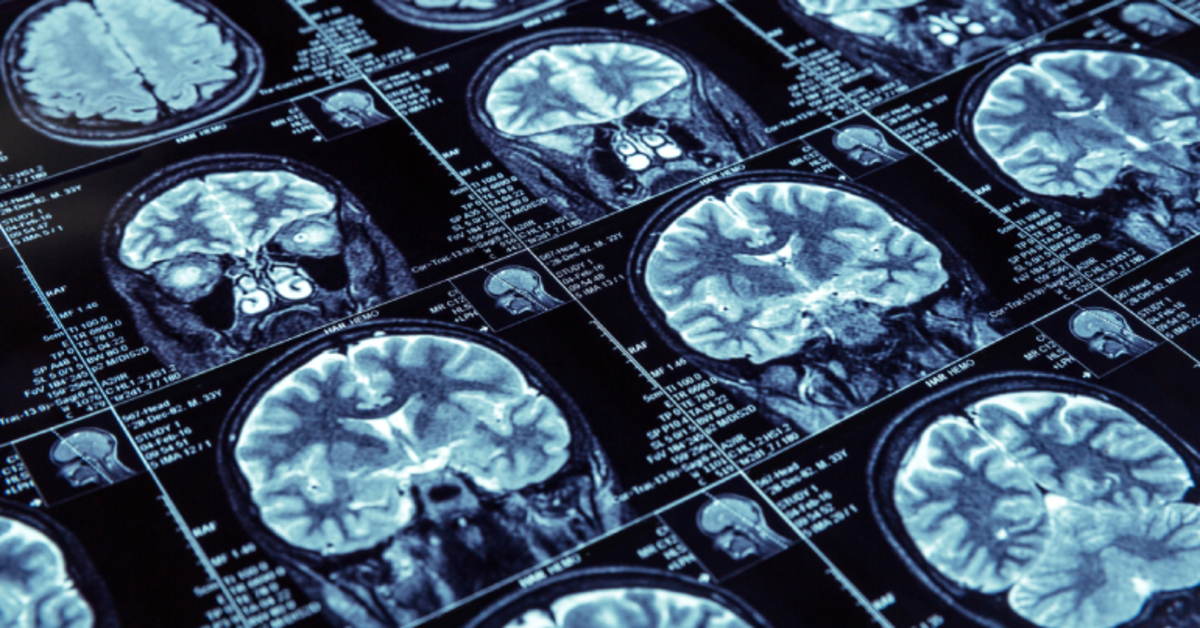

Biz unutkanlık şikayeti olan kişilerde öncelikle hastayı dinliyoruz. Bazı laboratuvar incelemeleri yapıyoruz. Bazen beyin görüntüleme incelemeleri yapıyoruz. Hastayı muayene ederek bu var olan görüntüleme ve verilerle beraber evet bu Alzheimer olabilir, hangi evresinde olabilir, veya demans dediğimiz nörolojik hastalıklarda da olabilir diyoruz.